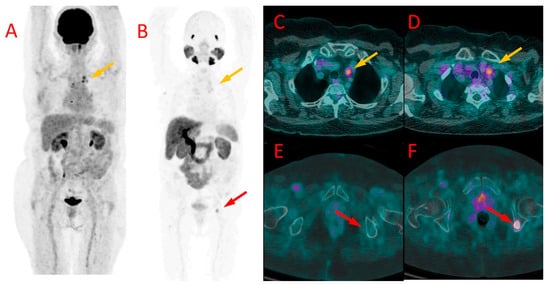

Figure 1. Primary breast lesions in the right breast depicted in PET/CT in patient #1. The first lesion is visible in PET/CT performed with [18F]FDG (A) and [18F]PSMA-1007 (red arrow) (B). A second lesion, located slightly below, was visible in [18F]PSMA-1007 (blue arrow) (D) but not with [18F]FDG (C). Both lesions were histologically confirmed as TNBC.

3.1. Local Disease

In the only treatment-naive patient (#1), both PET/CT modalities showed increased radiopharmaceutical uptake in the tumor of the right breast. The tumor had a diameter of 10–12 mm and showed a higher uptake of [18F]PSMA-1007 (SUVmax 6.0, TBR 2.8) than [18F]FDG (SUVmax 3.4, TBR 2.8). In addition, the 18F-PSMA PET/CT showed another focus of radiotracer accumulation in the same breast that was not present in the [18F]FDG PET/CT. The second focus was verified as a second focus of TNBC (Figure 1).